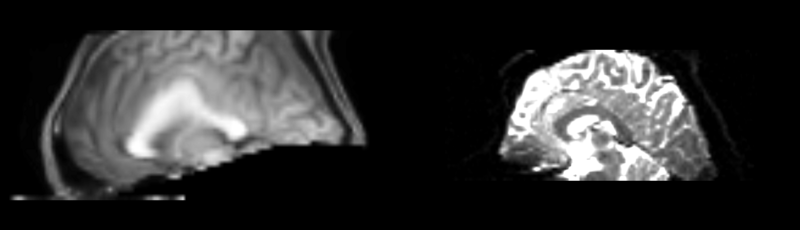

Registration of t1 weighted image to DTI space via a linear, then affine, then bspline registration.

current15:32, 4 May 2009Thumbnail for version as of 15:32, 4 May 20091,480 × 425 (166 KB)Rauscha (talk | contribs)Registration of t1 weighted image to DTI space via a linear, then affine, then bspline registration.